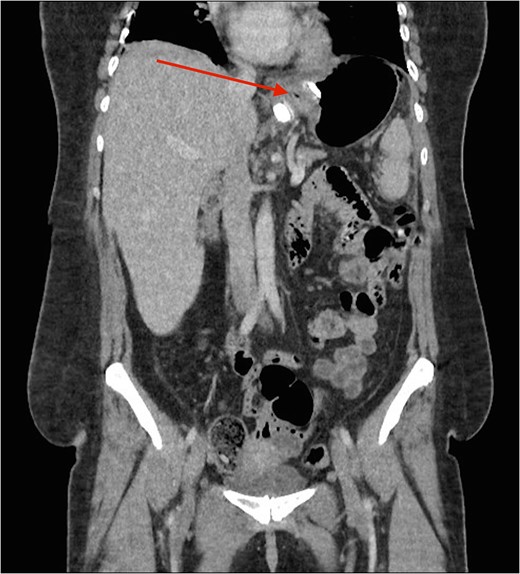

Cross section CT image demonstration the site of the band with no collection (red arrow).

CT image demonstrating the air loculation site next to the band (red arrow).